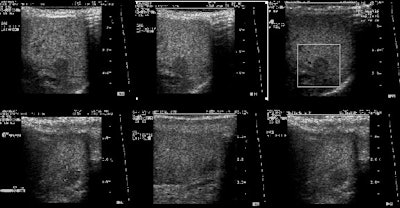

|

Benign adrenal lesion with FDG uptake: The patient shown below had a left adrenal mass which had remained stable for 2 years (white arrow). The stability over time and CT features would be consistent with a benign adrenal lesion- likely an adenoma. Note the marked FDG uptake within the mass on PET imaging (black arrows). Benign adrenal adenomas can accumulate FDG resulting in false positive exams. The use of PET/CT has been shown to improve the specificity of the PET exam. |

|

|